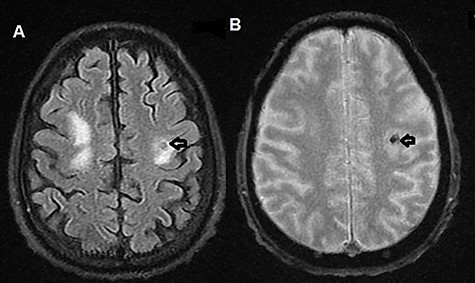

The patient was admitted to the hospital. Brain magnetic resonance imaging (MRI) revealed multiple multifocal hemorrhagic lesions with surrounding edema involving the cerebellum and both cerebral hemispheres, consistent with hemorrhagic metastatic lesions (Figs 1A, B and 2A, B).

(A) T2-weighted MRI axial image showing left parietal isointense lesion with surrounding edema (black arrow); (B) T2-weighted MRI axial gradient echo sequence showing left parietal lesion compatible with hemorrhagic foci (black arrow).